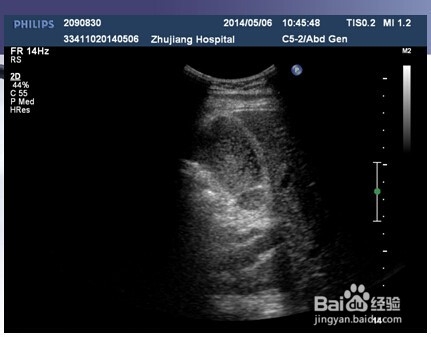

2、二:急性胆囊炎。